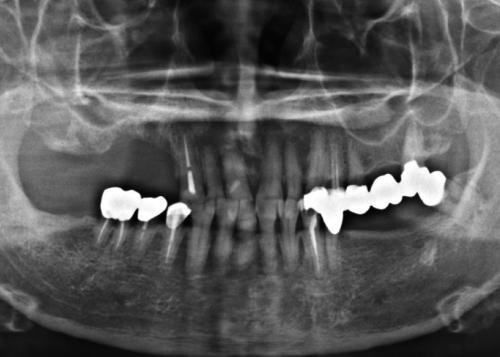

The aim of this study is to report a case of oral bisphosphonate-related osteonecrosis of the jaw (BRONJ) resulting in implant failure.

A patient suspected of having BRONJ was referred to the Department of Periodontology, Kyung Hee University School of Dentistry for the evaluation and treatment of exposed bone around implants.

The patient, who had been taking oral bisphosphonates (BPs) for about a year, was successfully treated with systemic antibiotics, chlorhexidine mouth rinse, explantation, and surgical debridement of necrotic bone.

The results of this case suggest that a patient taking BPs orally should be treated cautiously. Appropriate management including cessation of BPs and respective dental treatment may reduce the development of BRONJ.